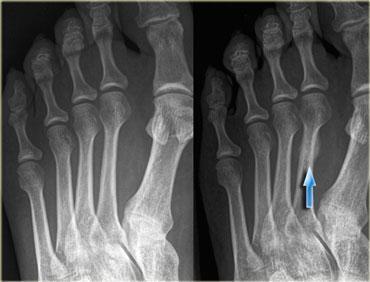

Gãy xương do stress điển hình tại thân xương đốt bàn chân thứ hai đoạn xa không thấy trên phim X-quang ban đầu (trái). Hình thành can xương được thấy rõ tại lần chụp kiểm tra sau 4 tuần.

X-quang

X-quang có độ nhạy 15-35% trong việc phát hiện gãy xương do stress ở lần chụp ban đầu, tăng lên 30-70% khi chụp kiểm tra do phản ứng xương trở nên rõ ràng hơn.

Do đó, các bác sĩ X-quang không nên yên tâm khi kết quả X-quang âm tính và cần chỉ định thêm các phương pháp chẩn đoán hình ảnh tiên tiến hơn.

Tuy nhiên, X-quang vẫn bắt buộc phải thực hiện để phát hiện các đường gãy rõ ràng và loại trừ các bệnh lý khác như nhiễm trùng hoặc u bướu.

Bên trái là hình ảnh của bệnh nhân nữ 42 tuổi, thường xuyên đi bộ đường dài và bị đau vùng mu bàn chân trong một tháng.

Trên phim X-quang ban đầu không thấy đường gãy.

Sau 4 tuần, phim X-quang kiểm tra cho thấy rõ ràng sự hình thành can xương tại vị trí gãy xương do stress.

Bên trái là hình ảnh của bệnh nhân nữ 28 tuổi với khởi phát đau gần đây tại vùng xương đốt bàn chân thứ hai.

Tại thời điểm thăm khám, phim X-quang âm tính với gãy xương đốt bàn chân thứ hai.